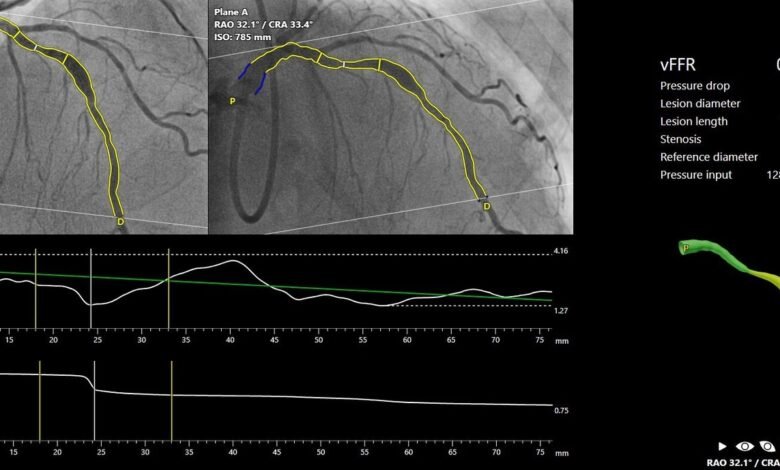

Pie Medical Imaging, ein weltweit führender Anbieter von Lösungen für die Herzbildanalyse, gibt das Ergebnis der FAST-III-Studie bekannt, das während der Sitzung „Late-Breaking Clinical Trials“ auf dem Kongress des American College of Cardiology (ACC) 2026 vorgestellt und im New England Journal of Medicine veröffentlicht wurde. Die Studie bestätigt die Nichtunterlegenheit der Revaskularisierung unter Verwendung von CAAS vFFR gegenüber der Revaskularisierung unter Verwendung von druckdrahtbasierter FFR.

FAST III war eine vom Prüfarzt initiierte, offene, multizentrische, randomisierte Studie, in der eine vFFR-geführte mit einer FFR-geführten Koronarrevaskularisation bei 2235 Patienten mit intermediären Koronarläsionen (definiert als 30-80%ige Stenose durch visuelle Beurteilung oder QCA) verglichen wurde. Intermediäre Läsionen wurden physiologisch anhand von vFFR oder FFR auf der Tischseite beurteilt und behandelt, wenn vFFR oder FFR ≤0,80 waren. Der primäre Endpunkt war ein Kompositum aus allen Todesursachen, einem Myokardinfarkt oder einer Revaskularisierung 1 Jahr nach der Randomisierung.

Dank der enormen Anstrengungen des leitenden Prüfers, Dr. Joost Daemen, Kardiologe im Thoraxzentrum am Erasmus University Medical Center in Rotterdam, Niederlande. 37 teilnehmenden Zentren und der ECRI (Sponsor der Studie) hat die Studie ihren primären Endpunkt erreicht: die MACE-Raten in der vFFR-geführten Gruppe und in der FFR-geführten Gruppe waren identisch.

„Die Ergebnisse von FAST III bestätigen die Sicherheit und Machbarkeit des Online-Einsatzes der vFFR als einfaches, minimal-invasives Instrument zur Anleitung der Revaskularisation bei Patienten mit intermediären Koronararterienläsionen, die eine physiologische Beurteilung der Läsion benötigen. Die Technologie hat das Potenzial, den Einsatz der Physiologie zu verstärken, was die Prognose von Patienten verbessern könnte, bei denen die Entscheidung zur Revaskularisierung intermediärer Koronararterienläsionen immer noch weitgehend auf Augenmaß beruht. Der Einsatz der vFFR macht Führungskatheter, invasive Koronararterieninstrumente und hyperämische Wirkstoffe überflüssig, die mit Risiken und Unannehmlichkeiten für den Patienten verbunden sind„, so Dr. Joost Daemen.